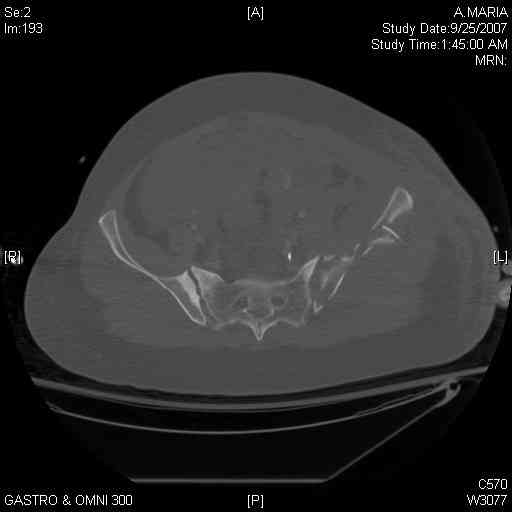

It's a comminuted iliac fracture involving the GS notch and all that

implies...use the lateral interval of an ilioinguinal, sequentially reduce,

and fix...if you want to, you can attach the dominant unstable fragment to

both the stable posterior iliac fragment and also to the anterolateral portion of the sacrum using plates...if you choose to anchor to both, the implants get congested on the iliac side of the SI joint so be precise with contouring and such applications...perhaps and based on the images shown, an iliosacral screw would only augment the construct if applied to the second sacral segment (but this is difficult to assess on the images shown). The crest components can be held securely with screws and/or peripheral plating.

Thanks. I probably didn't include enough images on the CT, but it didn't look to me like an SI screw would be of value except into S2, which I am not

comfortable placing. I will post finals if the neurosurgeons let me operate on her. ICPs still a problem.